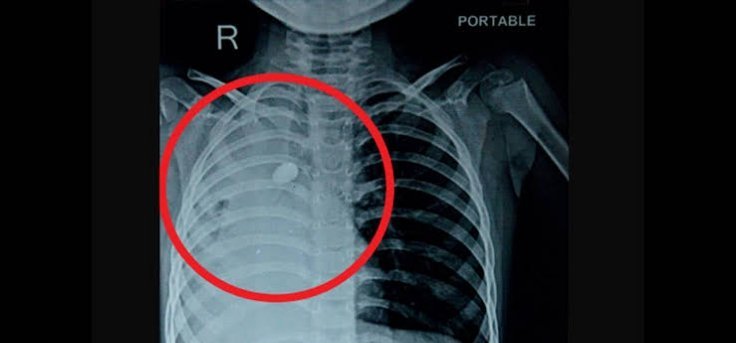

राज्य UTTARAKHAND: सांस नली में फंसी ‘गिट्टी’, संकट में था मासूम का जीवन, AIIMS ने लौटाई सांसें admin July 31, 2024 0